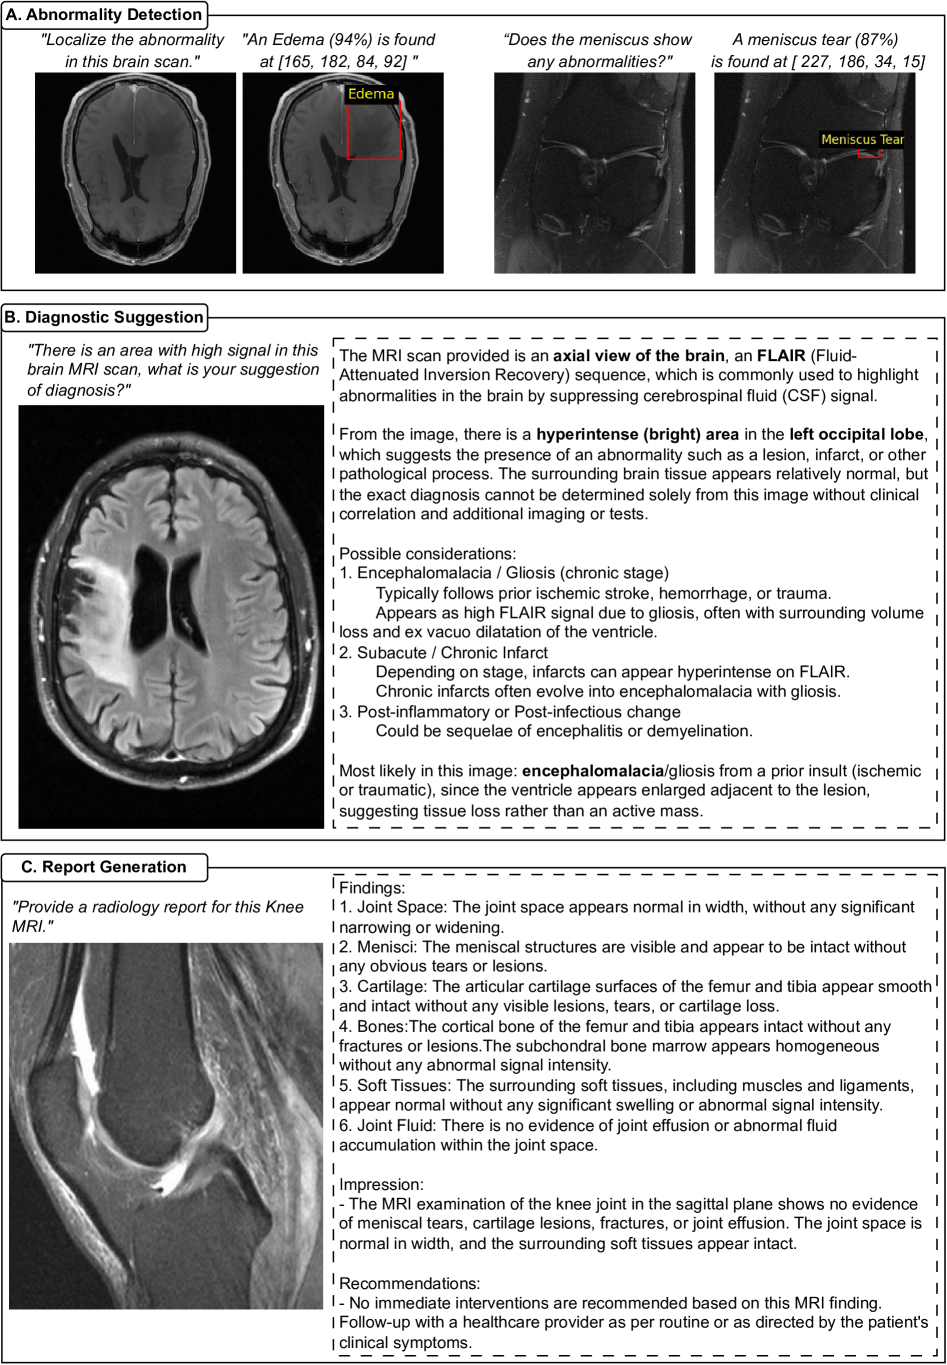

Refer to caption

Figure 4: Qualitative results of OmniMRI on higher-level tasks. (A) Abnormality detection. The model identifies and localizes brain edema and meniscus tears in the knee, producing bounding boxes. (B) Diagnostic suggestion. OmniMRI generates structured diagnostic reasoning. In the brain MRI example, the model highlights a hyperintense region in the occipital lobe and provides differential considerations (encephalomalacia, chronic infarct, post-inflammatory change), before suggesting the most likely diagnosis. (C) Report generation. OmniMRI produces coherent radiology reports that capture anatomical context, pathological findings, impressions, and recommendations.

Abnormality Detection OmniMRI demonstrates the capability to detect and localize abnormalities across diverse anatomical regions by generating bounding boxes and region-level predictions. As shown in Figure 4A, the model accurately identifies edema in the brain, producing bounding boxes with high confidence scores that align closely with radiologically confirmed pathological regions. Notably, OmniMRI also captures subtle abnormalities such as meniscal tears in the knee, which are often visually challenging to detect. These results highlight the model’s ability to perform both coarse- and fine-grained abnormality detection across different organ systems, supporting diagnostic workflows that require sensitivity to subtle imaging findings while maintaining robustness across broader pathologies.

Diagnostic Suggestion When prompted with diagnostic queries, OmniMRI produces structured, clinically oriented suggestions that integrate imaging observations with medical reasoning. As illustrated in the brain MRI example (Figure 4B), the model identifies a hyperintense region in the left occipital lobe and provides a differential diagnosis that includes encephalomalacia, chronic infarct, and post-inflammatory changes, before suggesting the most likely interpretation. This output demonstrates OmniMRI’s capacity to move beyond binary classification, instead offering interpretive reasoning that mirrors radiological practice. By synthesizing imaging features with clinical knowledge, OmniMRI enables hypothesis generation and decision support, highlighting its potential role as an assistive tool in radiology workflows and multidisciplinary care.

Report Generation OmniMRI is capable of generating coherent, structured, and clinically meaningful radiology reports directly from MRI images and task-specific instructions. In the knee MRI example, the model-produced report systematically addresses each relevant component of interpretation: Joint space evaluation; Menisci morphology and integrity; Cartilage thickness and defects; Bone structures and marrow signal; Surrounding soft tissues. The report then concludes with a diagnostic impression and actionable recommendations, mirroring the organization and language of expert radiology practice. By providing both anatomical context and pathology assessment in natural language format, OmniMRI outputs demonstrate not only interpretive accuracy but also workflow relevance. These results highlight the model’s potential to unify image analysis and structured reporting, thereby reducing documentation burden for radiologists while maintaining clinical fidelity and consistency.